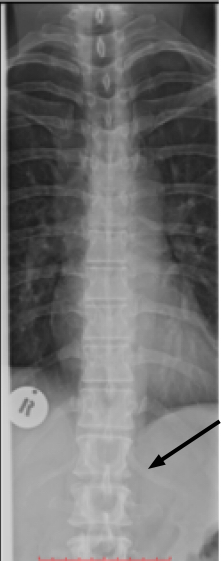

This may be further complicated by the presence of a short leg, causing a distortion in the pelvis and a lumbar scoliosis extending up into the mid back and cervical spine where further problems are caused. It is not unusual for these patients to have neck and thoracic pain, in addition to lower back and thigh symptoms.

The mild lumbar scoliosis continues up into the torso, resulting in pain in the midback and neck.

Rudimentary ribs are seen at T12, a common feature of a sacralisation or lumbarisation. Naming is not important; whether the last discrete vertebra is L4 or 5 makes no difference. What is significant is the presence of a transitional segment, asymmetrical facets, a transverse ilio anomalous joint and those little appendages arrowed at the thoraco lumbar junction.

These anomalies sometimes produce quite unusual and even bizarre patterns of lower and upper lumbar pain with diverse thigh and calf radiation.